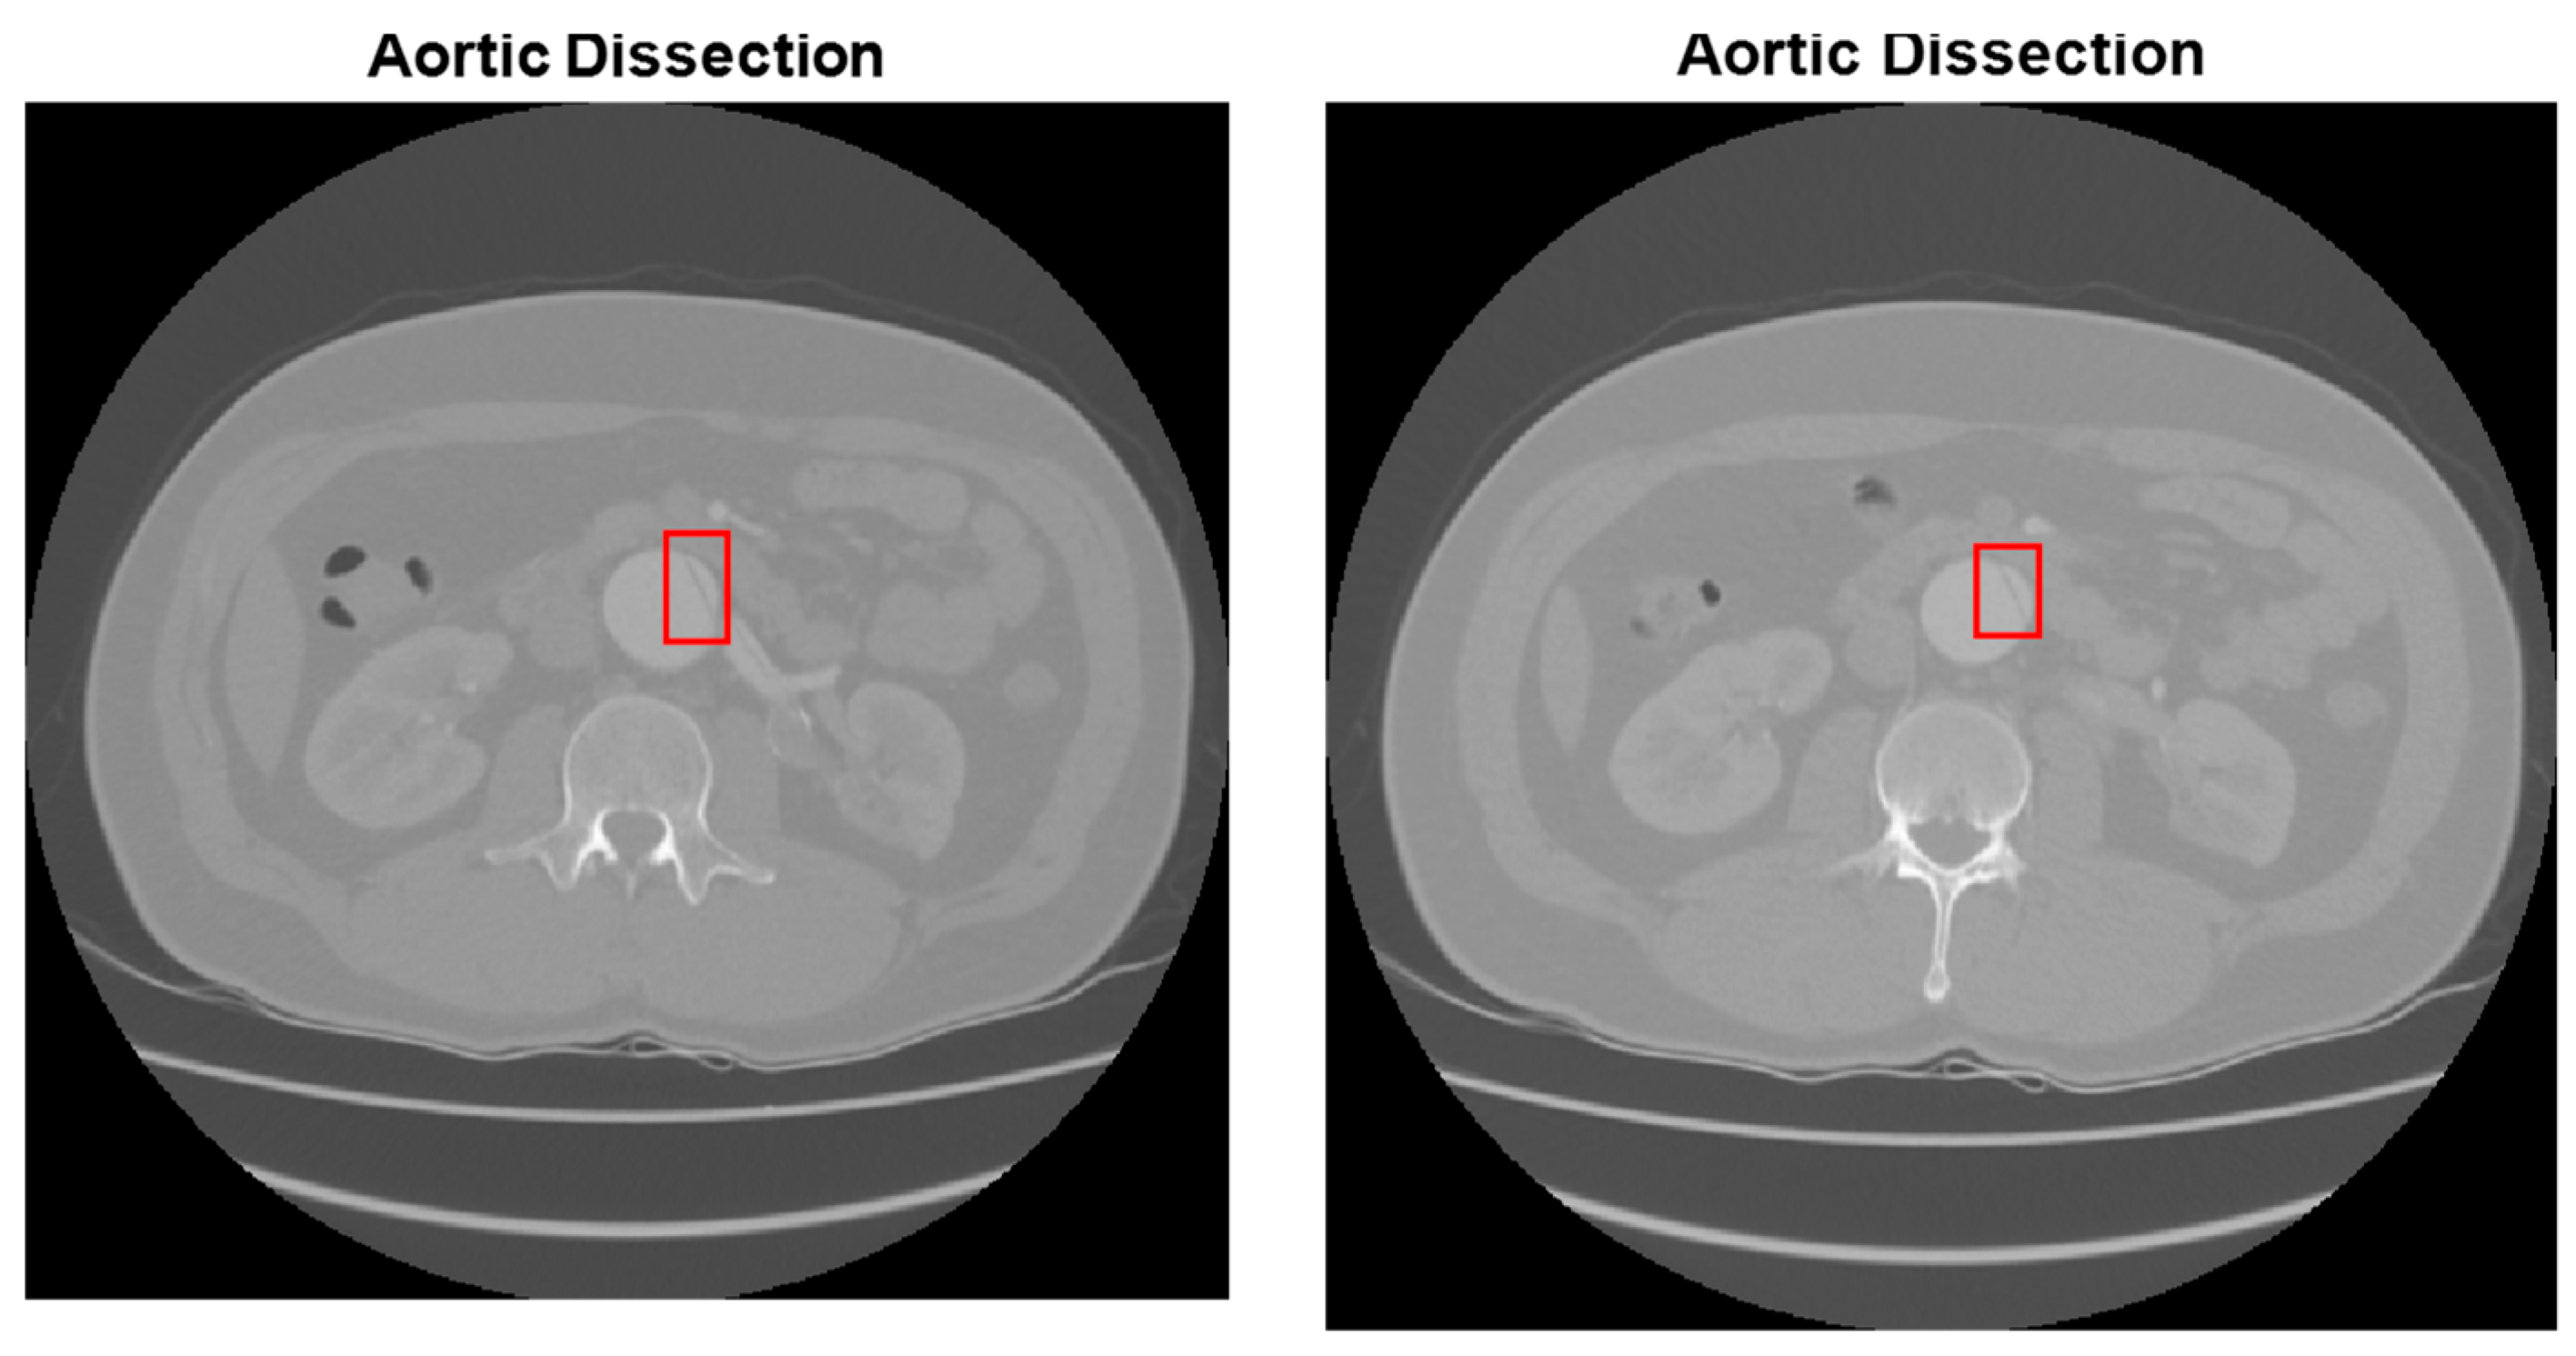

2.3. Abdominal Aortic Dissection (AAD) Detection